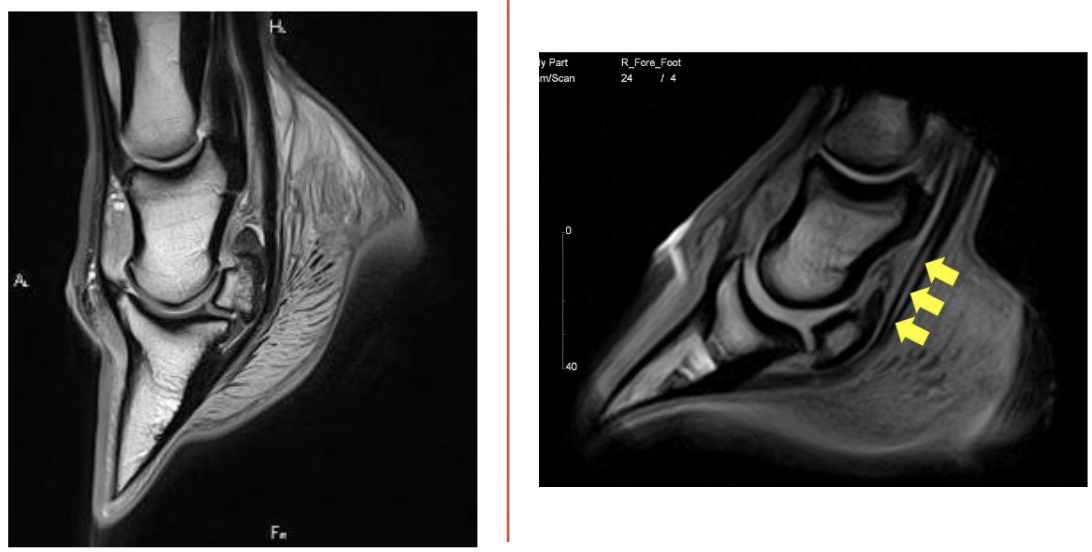

what is this

left= normal

right= deep digital flexor tendonitis

yellow arrows= tear in deep digitial flexor tendon

what is this

left= normal

right= suspensory ligament desmitis

cloudyness (red arrow) is showing fluid injury

white lines on left image is normal for comparison